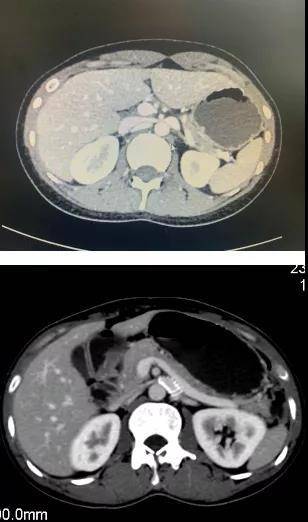

天津市第三中心医院泌尿外科主任陈方敏教授介绍说 , 胡桃夹综合征又叫做左肾静脉压迫综合征 , 是指左肾静脉穿行于肠系膜上动脉与腹主动脉之间 , 受到两者的挤压 , 或穿行于腹主动脉与脊柱之间的间隙受到挤压的一系列症状 , 患者常伴有左肾静脉血流速度的下降、受压处远端静脉的扩张等情况 。

该治疗方法是术前通过影像学精准测量夹角大小、肾静脉内径等参数 , 手术时运用腹腔镜或机器人将血管外支架安全植入患者人体 , 为左肾静脉提供宽敞的“隧道” , 解除血管压迫、梗阻 。 该手术优势是支架牢固、稳定 , 术后不需口服抗凝药物 , 疗效较为可靠 。